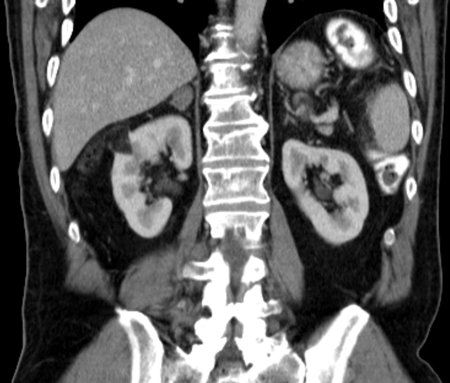

Renal angiomyolipoma: right kidney lesion in CT; source: Hellerhoff, Wikimedia Commons